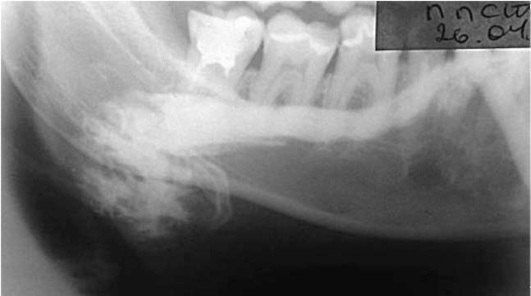

Пороки развития выводных протоков слюнных желез выявляются на сиалограммах в виде их значительного расширения (эктазии). Наиболее часто расширяются околоушной (рис. 6.1) или поднижнечелюстной протоки, что приводит к развитию хронического сиаладенита или слюннокаменной болезни. Нередко встречаются дивертикулы протока в виде ограниченного слепого выпячивания его стенки (рис. 6.2). Если таких дивертикулов очень много, то речь идет о хроническом паренхиматозном паротите или сиалодохите.

Рис. 6.2. Дивертикул в области левого поднижнечелюстного протока